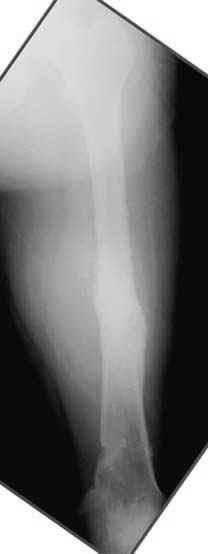

Несколько снимков из моей коллекции, чтобы разьяснить, почему мы до сих пор делаем различные варианты остеотомии.

На рисунке N1 предоперационный план лечения ложного сустава шейки бедра- линия ложного сустава, угол и направление введения импланта, клиновидная остеотомия в градусах и миллиметрах, второй снимок после коррекции, расчет, на сколько удлиняется конечность и размеры импланта;

N3 рисунок окончательный снимок, после операции моя рентгенограмма должен выглядеть примерно как эта картина. На N4 снимке клин перед удалением; N5 послеоперации 3 нед.; N6 окончательная рентгенограмма.